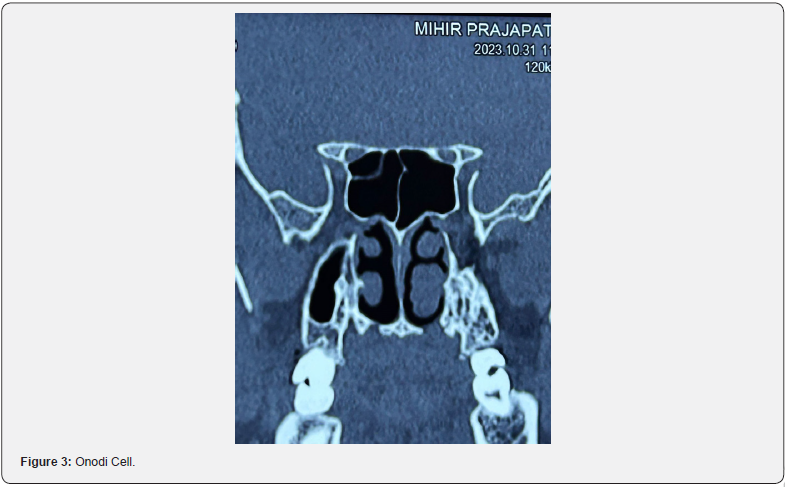

A retrospective study was conducted amongst 200 patients over a period of one year (2022-2023) at Sharda hospital Greater Noida . Patients with various symptoms of chronic rhinosinusitis were subjected to non-contrast enhanced Computed Tomography of nose and paranasal sinuses. Anatomic variations of the sinonasal cavities were assessed in the CT images, and prevalence of each was noted. The study included patients with age ≥ 18 having chronic rhinosinusitis and patient having chronic rhinosinusitis with or without polyposis who were advised NCCT nose and PNS after thorough examination. Patients having any previous nasal surgery or trauma, who did not consent for the study and patients less than 18 years were excluded from the study (Figure 2-4).

Furthermore, orbital injuries after ethmoidectomy can be more likely when Haller cells are present [16]. Badia et al. [15] reported the presence of Haller cells in 10-15% Caucasian and 1-9% Chinese group respectively [15]. The Onodi cell (sphenoethmoid air cell), is a posterior ethmoid cell that is closely linked to the optic nerve. It pneumatises far laterally and somewhat superiorly to the sphenoid sinus.

The internal carotid artery and optic nerve are more vulnerable to injury when Onodi cells are present. Thus, identification before surgery is of utmost importance [3,13]. Its frequency is reported to fluctuate widely, from 2% to 50%. [16]. In Chinese population, presence of Onodi cells has been reported as 20-30 [15]. In the adult group, 48% of Onodi cells were found, according to Bansberg et al. [17]. In the current study, incidence of Haller cells was found in 5.0% and Onodi cells were found in 4.5% of subjects which comparable to previous studies.